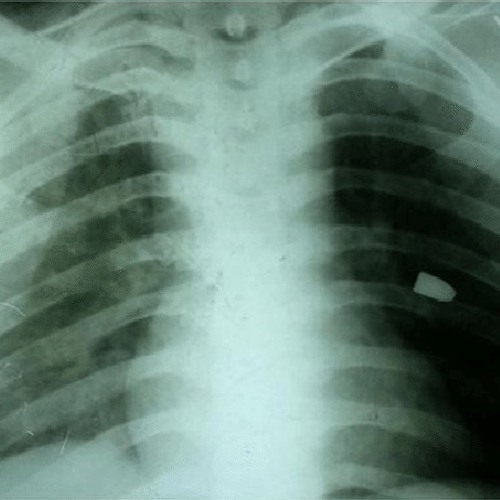

GUNSHOT WOUND TO CHEST | Buyxraysonline

GUNSHOT WOUND TO HEAD | buyxraysonline